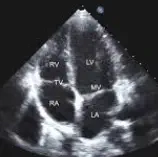

Ехокардиографија

Ехокардиографијата е неинвазивна дијагностичка процедура што користи ултразвук

за да создаде детални слики на срцето. Оваа метода овозможува проценка на

структурата и функцијата на срцевите залистоци, комори, ѕидови и крвни садови.

Се изведува со помош на уред наречен ехокардиограф, кој емитува ултразвучни

бранови и ги регистрира одбиените сигнали за да формира визуелна претстава.

Постапката е безболна, безбедна и не вклучува зрачење, што ја прави широко

применлива. Се користи за дијагностицирање на состојби како срцева слабост,

вродени срцеви аномалии, болести на залистоците и кардиомиопатии.

Ехокардиографијата може да биде трансторакална или трансезофагеална, во

зависност од потребите. Резултатите помагаат во планирањето на лекувањето и

следењето на срцевите заболувања.